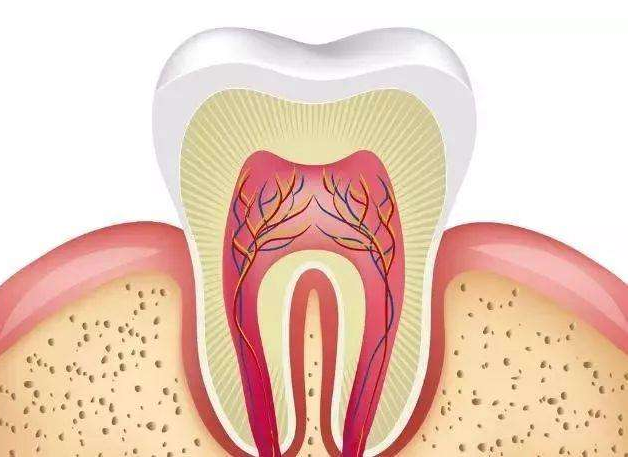

3、急慢性牙髓炎

临床表现:可有自发性、阵发性、放射性疼痛且不能定位,冷热刺激加重,可有扣痛或不适。慢性牙髓炎可有长期牙痛史,多可定位患牙,稍有扣痛或不适。

治疗方法:根管治疗杀神经,做牙套。

4、根尖周炎

临床表现:有可定位的自发性跳痛、咬合痛,不敢用患牙咀嚼食物,扣痛严重,牙髓活力测试无反应,相应牙的根部红肿、扪痛、松动,并可诱发间隙感染、淋巴结肿大压痛及全身症状。

治疗方法:根管治疗杀神经,做牙套。